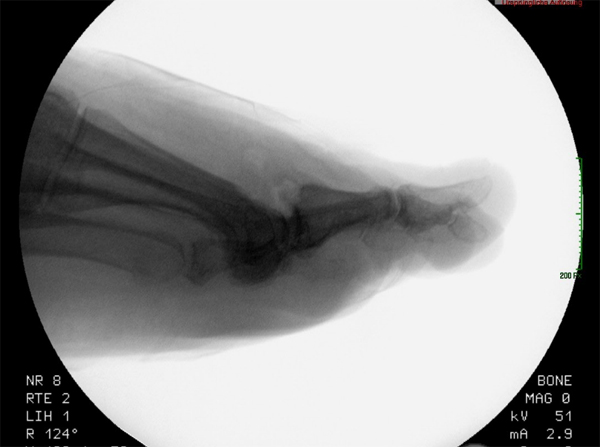

• Belastete Röntgenaufnahmen in 3 Ebenen.

Beim Hallux rigidus Stadium II beobachtet man die Ausbildung von Osteophyten dorsal, medial und lateral sowohl metatarsal als auch an der Basis des Grundphalanx bei noch ausreichender Knorpelbedeckung der plantaren Gelenkabschnitte 12. Diese führen zum Impingement, zur Einschränkung der Extension im Großzehengrundgelenk und konsekutiver Störung des Abrollverhaltens des Fußes.